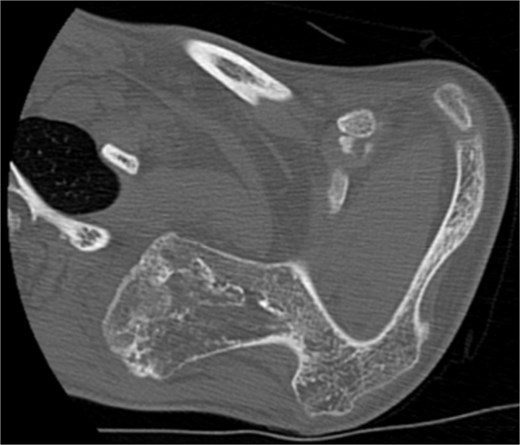

The imaging investigation was initiated by our department, as we were clinically suspicious of the presence of osteochondromas, due to the history of HME in both patients. Both patients were subscribed an anteroposterior X-ray of left shoulder and a CT scan for pre-operative planning. Also, radiographic evaluation of both knees and left forearm were taken and revealed multiple exostoses as a part of the HME follow-up that both girls underwent. The CT scan of the 14 year old patient demonstrated three bony lesions arising from the ventral aspect of left scapula. The largest one extruded from superior angle heading medially to the vertebral bodies. The other two smaller arose one from the lateral angle and one from the inferior angle. The CT scan of the 9 year old patient revealed one bony lesion arising ventrally from the superior angle of the left scapula heading medially as well (Figs 2 and 3). The diagnosis of VSO was made in both cases.

CT of the 14-year-old patient showing both lesions in sagittal plane.